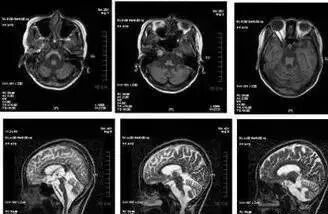

脑萎缩原本是在做头颅CT或MRI检查时,发现脑组织体积减小和脑室扩大等而命名的,因此,脑萎缩不是一种病,是许多疾病的神经影像学表现。

而病理学意义上的脑萎缩,是指因衰老、脑部创伤、神经系统疾病、感染等原因导致脑细胞异常减少、脑组织发生萎缩的一种现象。

2010年初,老侯带着两个孩子来到了医院做了核磁共振检查,从而剖析大脑的结构:两个孩子都有小脑萎缩的情况。而从遗传学上推断,这属于遗传性疾病,是家族性的。